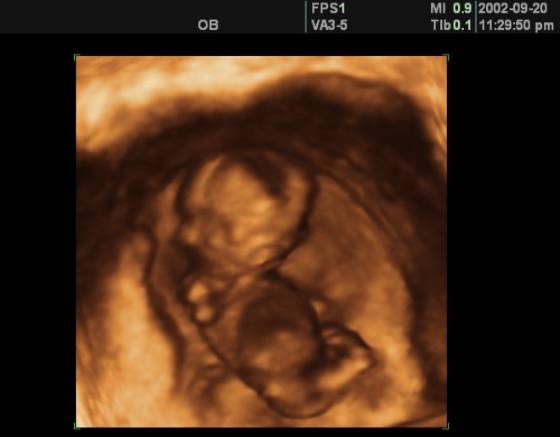

Собственное кровообращение у плода начинает функционировать с конца второго месяца его антенатальной закладки, обеспечивая кровоснабжение головного мозга, других жизненно важных органов.

Схема, представляющая кровообращение у плода, отличается от схемы кровообращения после рождения – кровоток у плода организован с помощью дополнительных гемодинамических шунтов.

- Стадия трубчатого сердца. Начинается на 2-й неделе эмбриогенеза. Сердечко – простая трубка, через которую напрямую протекает кровь.

- Стадия сигмовидного сердца. Начало 4-й недели. Уже есть один желудочек. Выделяют венозные отделы и артериальный ствол. Формируется две сердечных камеры. Появляются первые сердечные сокращения. Закладывается и начинает функционировать большой круг кровообращения.

- Трехкамерное сердце. 5-я неделя. Развивается межпредсердная перегородка. Овальное окно сообщает предсердия между собой.

- Четырехкамерное сердце. 6-я неделя. Разделяется желудочковая камера, появляются атриовентрикулярные клапаны. Аорта и лёгочный ствол делят артериальный ствол.